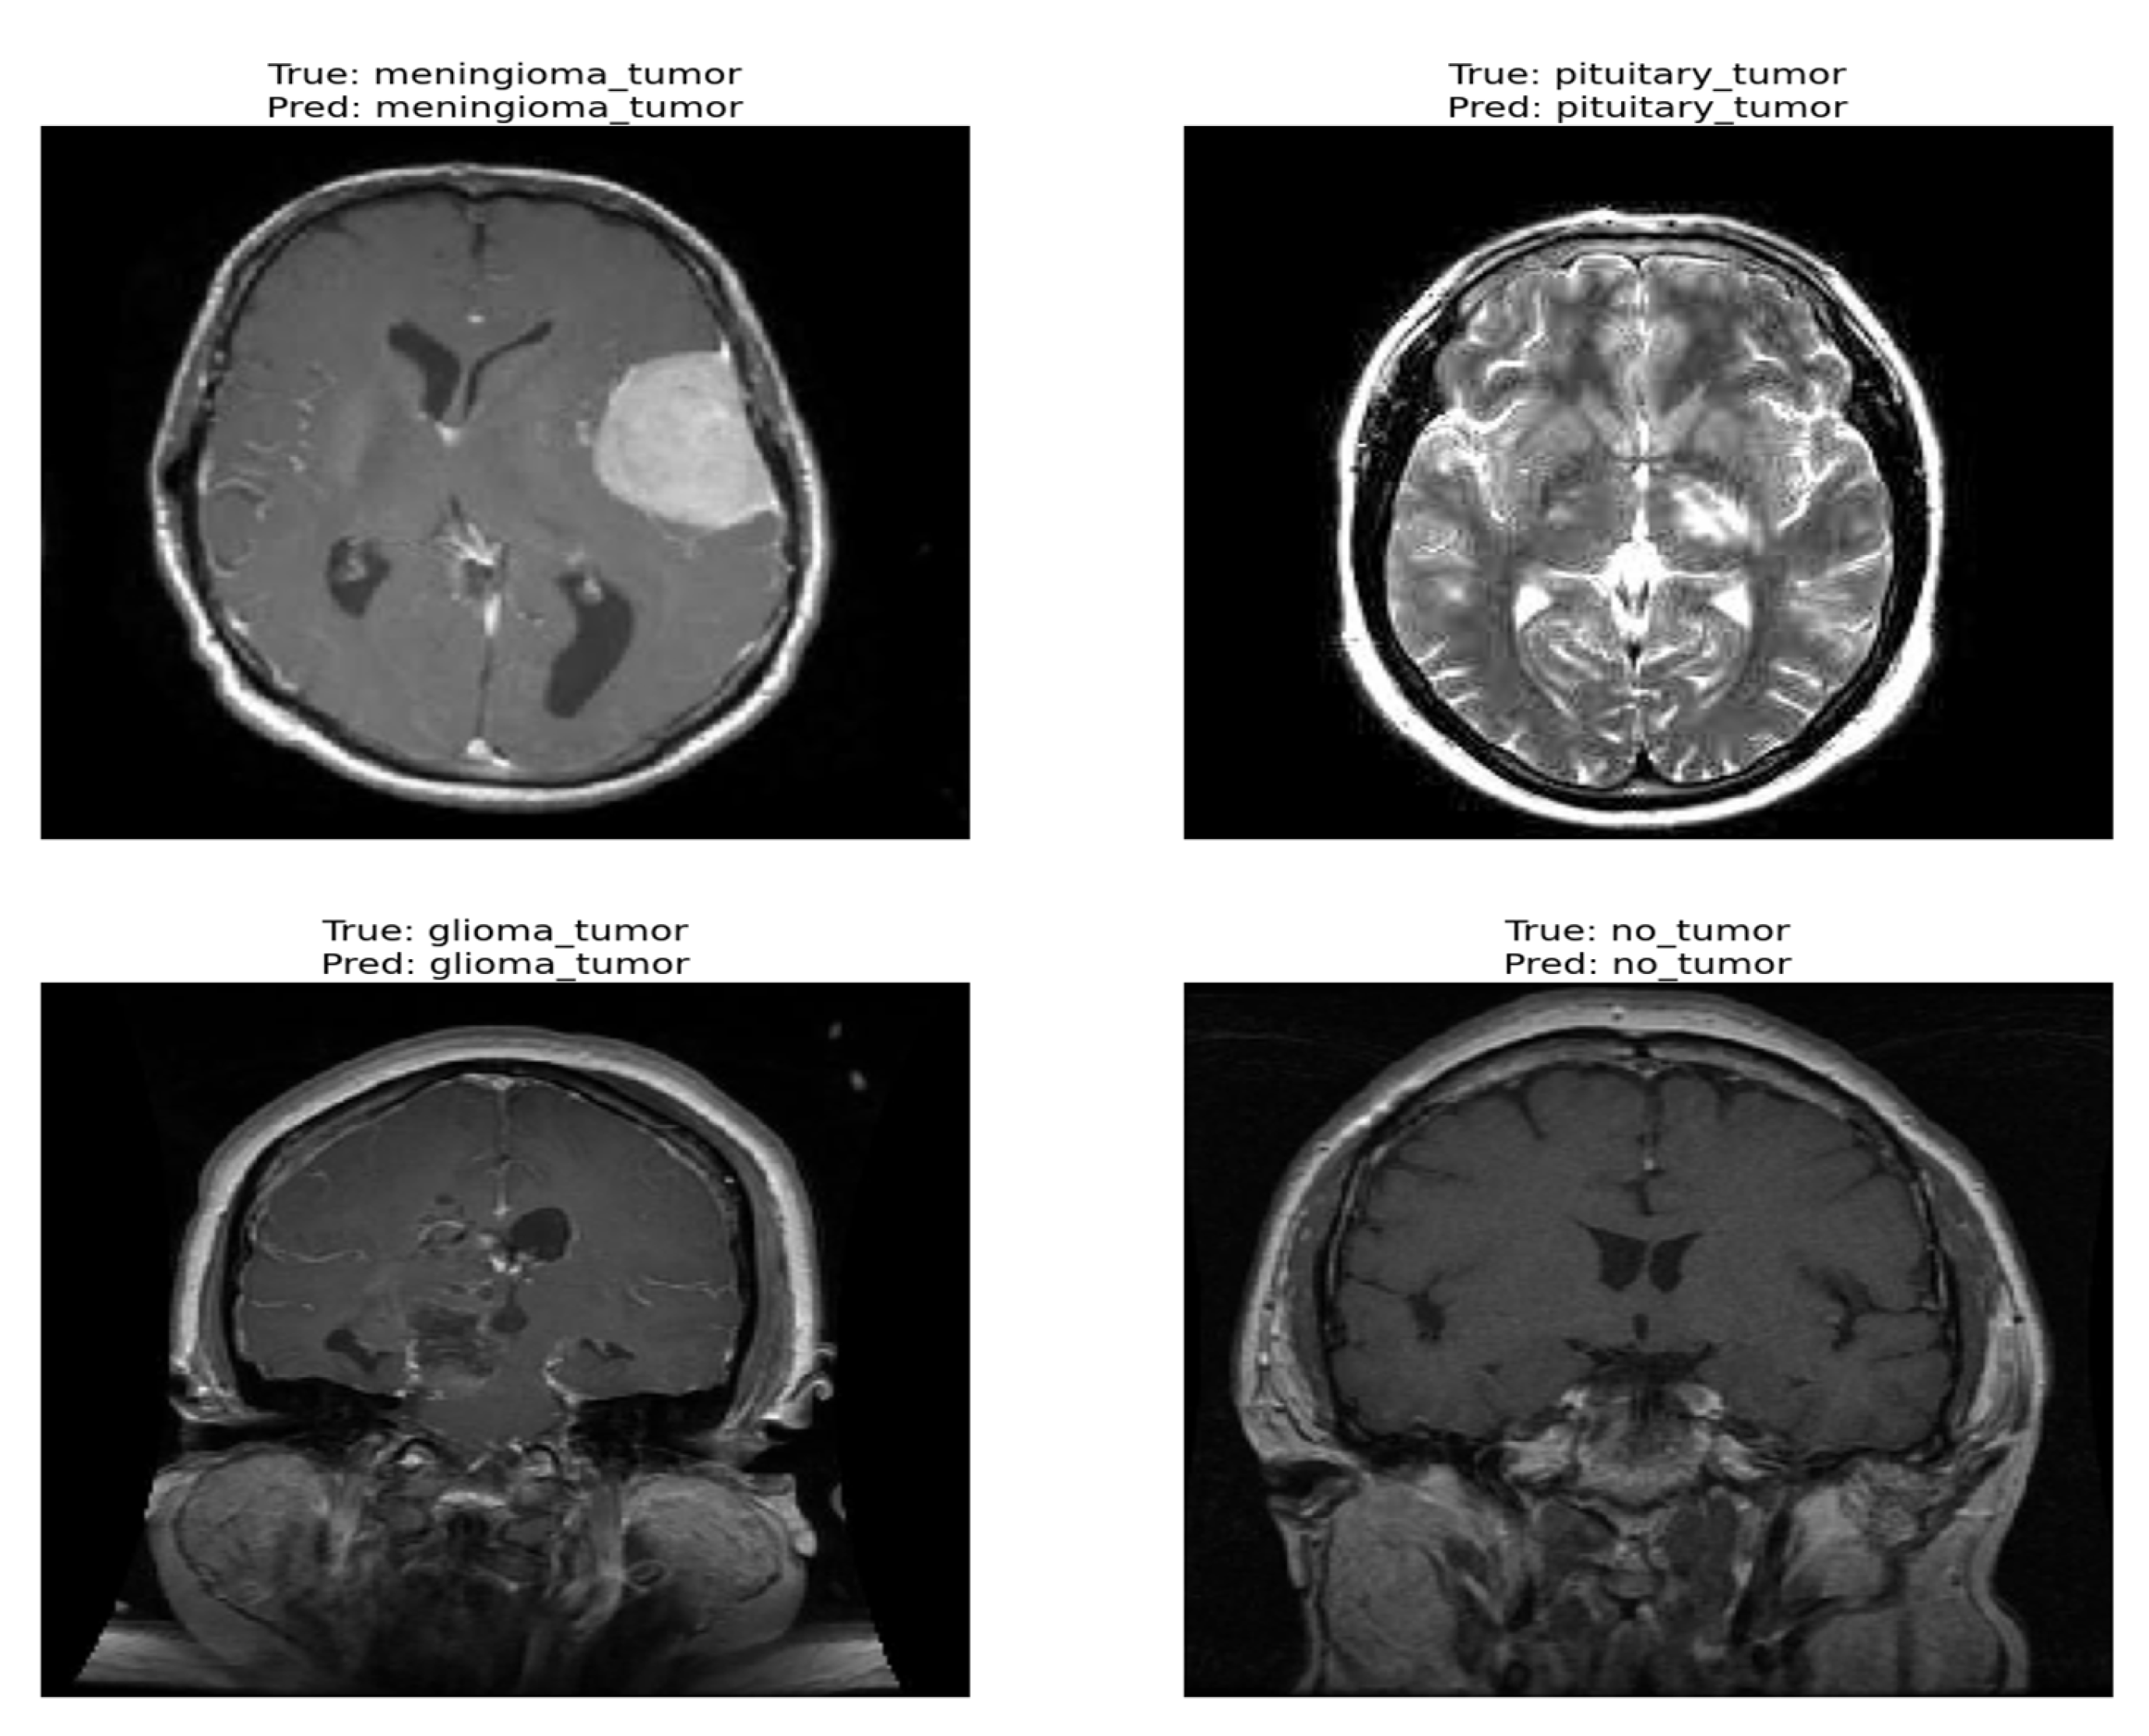

The confusion matrix was utilized to provide additional insights into the model’s performance by summarizing the correctly and incorrectly classified instances. For the validation set of 857 images, the model correctly identified 841 images, while 16 images were misclassified as shown in Figure 4. Furthermore, Figure 5 and Figure 6 present the classification outcomes of the proposed study, illustrating both accurate and inaccurate classifications.

Figure 5.

Correct classification result of proposed ViT model.

Figure 5 and Figure 6 present the visual results obtained from our FT-ViT model. These figures serve as compelling evidence of the model’s efficacy in accurately classifying different tumor types. As depicted in Figure 5, the proposed FT-ViT model exhibits remarkable performance, achieving an impressive accuracy of 98.13%. The high accuracy underscores the model’s capability to correctly identify tumor types with exceptional precision. However, there are instances where the FT-ViT model encounters challenges in accurately classifying tumor types. These instances are also reflected in the confusion matrix, which highlights the cases where the model misclassified tumor types. Figure 6 provides a visual representation of the results where the FT-ViT model encountered difficulties and failed to identify certain tumors accurately. The incorporation of both Figure 5 and Figure 6 allows us to comprehensively evaluate the FT-ViT model, highlighting its overall success in tumor classification, while also shedding light on areas for improvement.